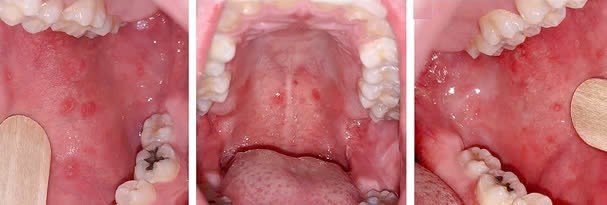

- Giai đoạn khởi phát (GĐ viêm long): trong 2 - 4 ngày. GĐ này BN sốt cao, viêm long đường HH trên và viêm kết mạc. Có thể thấy hạt Koplik là các hạt nhỏ có kích thước 0,5 - 1 mm màu trắng/xám có quầng ban đỏ nổi gồ lên trên bề mặt niêm mạc má (phía trong miệng, ngang răng hàm trên). Hạt Koplik thường xuất hiện một ngày trước phát ban và tồn tại 2 - 3 ngày sau khi ban xuất hiện.

Hạt Koplik